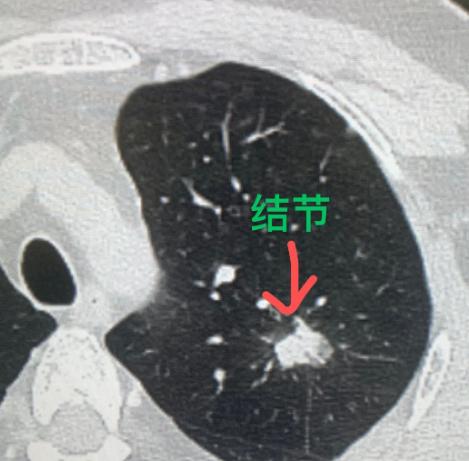

这一查,果然查出问题:左上肺有一个大约2厘米的结节,密度很高,从形态上看,肺癌的可能性很大。